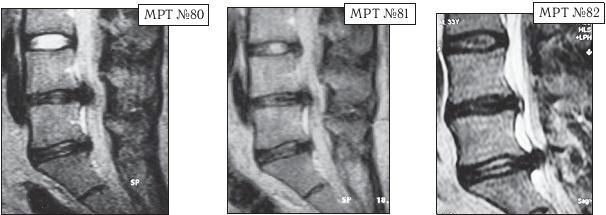

Следующий пример в продолжение нашей темы, как пациент поддался рекламе и обратился к мануальному терапевту, который гарантировал «полное избавление от болей». Данный пациент по профессии строитель. Испытывал периодические боли в поясничном отделе позвоночника с 1996 года. Неоднократно проходил медикаментозное лечение под наблюдением невропатолога. Диагностические обследования позвоночника в этот период лечения не проводились. В августе 2002 года во время санаторно-курортного лечения, по назначению лечащего врача, прошёл курс вытяжения позвоночника, после которого началось обострение, появилась боль и онемение в правой ноге. Во время стационарного лечения в неврологическом отделении провели МРТ-обследования (МРТ № 80) и порекомендовали проконсультироваться у нейрохирурга. Пациент проконсультировался у нейрохирурга, но от предложенной операции отказался. Под контролем специалистов лечился медикаментозно. В марте 2010 года, соблазнившись рекламой, данный пациент решил «навсегда избавится от болей в позвоночнике» и обратился к мануальному терапевту, который гарантировал «полное избавление от болей». Результатом этого «гарантированного лечения» (результат отображен на МРТ № 82) стала секвестрированная грыжа межпозвонкового диска и, естественно, значительное ухудшение самочувствия данного пациента.

На МРТ № 80 от 04.09.2002 года, наблюдается исправление физиологического лордоза, грыжа межпозвонкового диска в сегменте LIV—LV, стеноз спинномозгового канала на данном уровне, компенсированная спондилёзом протрузия в сегменте LV—SI

На МРТ № 81 того же пациента от 19.07.2007 наблюдается практически аналогичная с 2002 годом картина, с той лишь разницей, что грыжа межпозвонкового диска в сегменте LIv-Lv частично компенсировалась спондилёзом.

На МРТ № 82 того же пациента от 02.04.2010 наблюдается исправление физиологического лордоза, компенсированная спондилёзом грыжа межпозвонкового диска в сегменте LIV-LV, секвестрированная грыжа межпозвонкового диска в сегменте LV—SI абсолютный стеноз спинномозгового канала на данных уровнях.